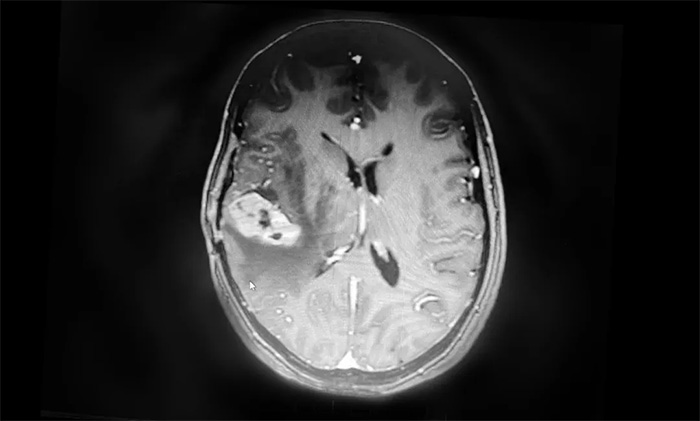

卢云鹤博士为患者进一步完善检查。MR检查示右侧颞叶内见环片状混杂信号,大小约20mm*18mm,强化与水肿明显。周围脑沟、裂显示欠清;右侧侧脑室受压变形,中线结构稍左偏,出现可疑脑膜转移。

▲ MR示右侧颞叶占位,占位效应明显

结合既往病史和影像学表现,卢云鹤博士认为,患者乳腺癌脑转移瘤复发可能性较大。虽然占位本身体积不大,但其水肿带已压迫临近脑室,患者出现头痛头晕症状,应考虑采取合适的方法积极给予治疗。